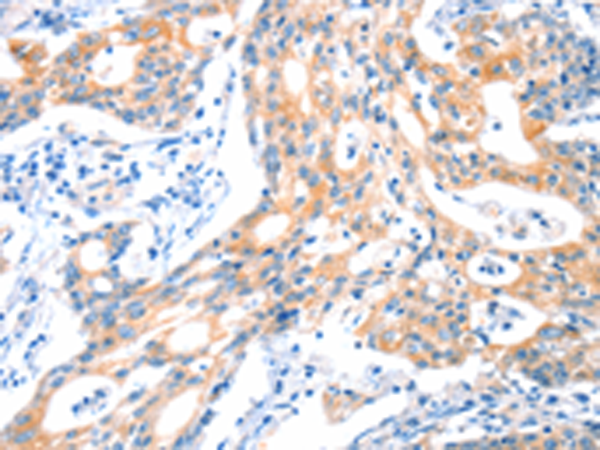

分类: 科研抗体货号: P11552别名: 5-HT3B应用: IHC反应种属: Human